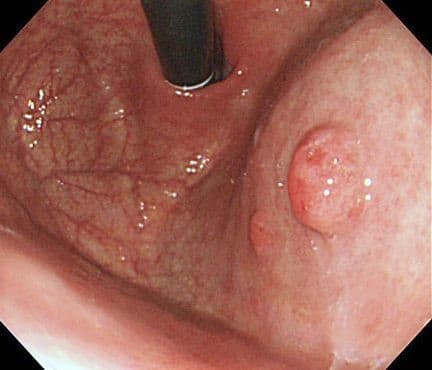

Эндоскопически они обычно гладкие, куполообразные (0-Is, 0-Isp тип), размерами от 5 до 15 мм в диаметре, хотя могут быть намного больше. Большие полипы становятся дольчатыми, расположенными на ножке (0-Ip тип), поверхность эпителия полипа нередко эрозирована, что может являться причиной хронической кровопотери и железодефицитной анемии. Редко поступают пациенты с признаками высокой непроходимости, вследствие обтурации или пролабирования полипа через привратник. Гиперпластические полипы возникают как гиперпролиферативный ответ на повреждение слизистой (эрозии, язвы). Длительное химическое воздействие соляной кислоты и наличие инфекции H.pylori могут быть первоначальной ступенью в их развитии.

Эндоскопически они представлены солитарным одиночным образованием дольчатой формы с бархатистой поверхностью. Хотя они могут быть найдены в любом отделе, наиболее часто локализуются в антральном отделе желудка.